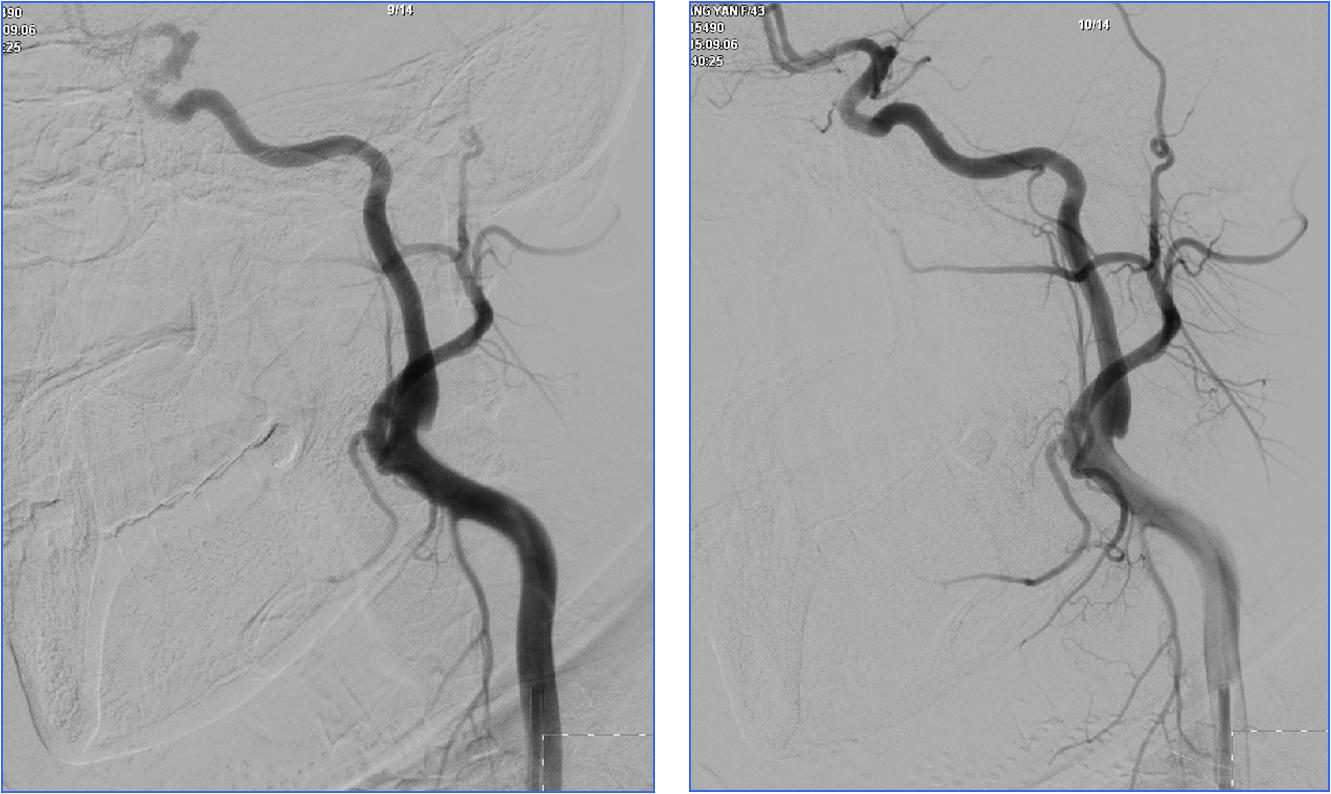

Case6 术后呼吸功能衰竭

》54岁,男,既往脑梗死、高血压病、糖尿病

》因头晕伴呕吐2天,9:50到达急诊

》10:08完成头CT检查

》15:30突发心跳骤停,行心肺复苏、气管插管

》NIHSS 30分

》15:55头MRA检查

》17:00行股动脉穿刺

》18:50结束手术

》术后24h NIHSS 10分

▼左椎动脉颅内段闭塞,脊髓前动脉代偿

▼右椎动脉颅外段闭塞

▼取栓后左椎动脉V4段残留狭窄

▼球囊成形,狭窄改善,不能维持

▼Wingspan支架置入

》11.30 13:00拔气管插管后不能呼吸,呼吸动度差,面部青紫,重新插管,spO2最低20%,意识不清,2小时后恢复。

》12.3 10:00再次拔管后仍不能呼吸,插管

》12.3 16:00行经皮气管切开。

》12.5 转普通病房后因血压高应用硝普钠后血压降至50mmHg,呼吸困难,青紫,昏迷,应用呼吸机后意识恢复。

》12.14自动出院,12.15死亡